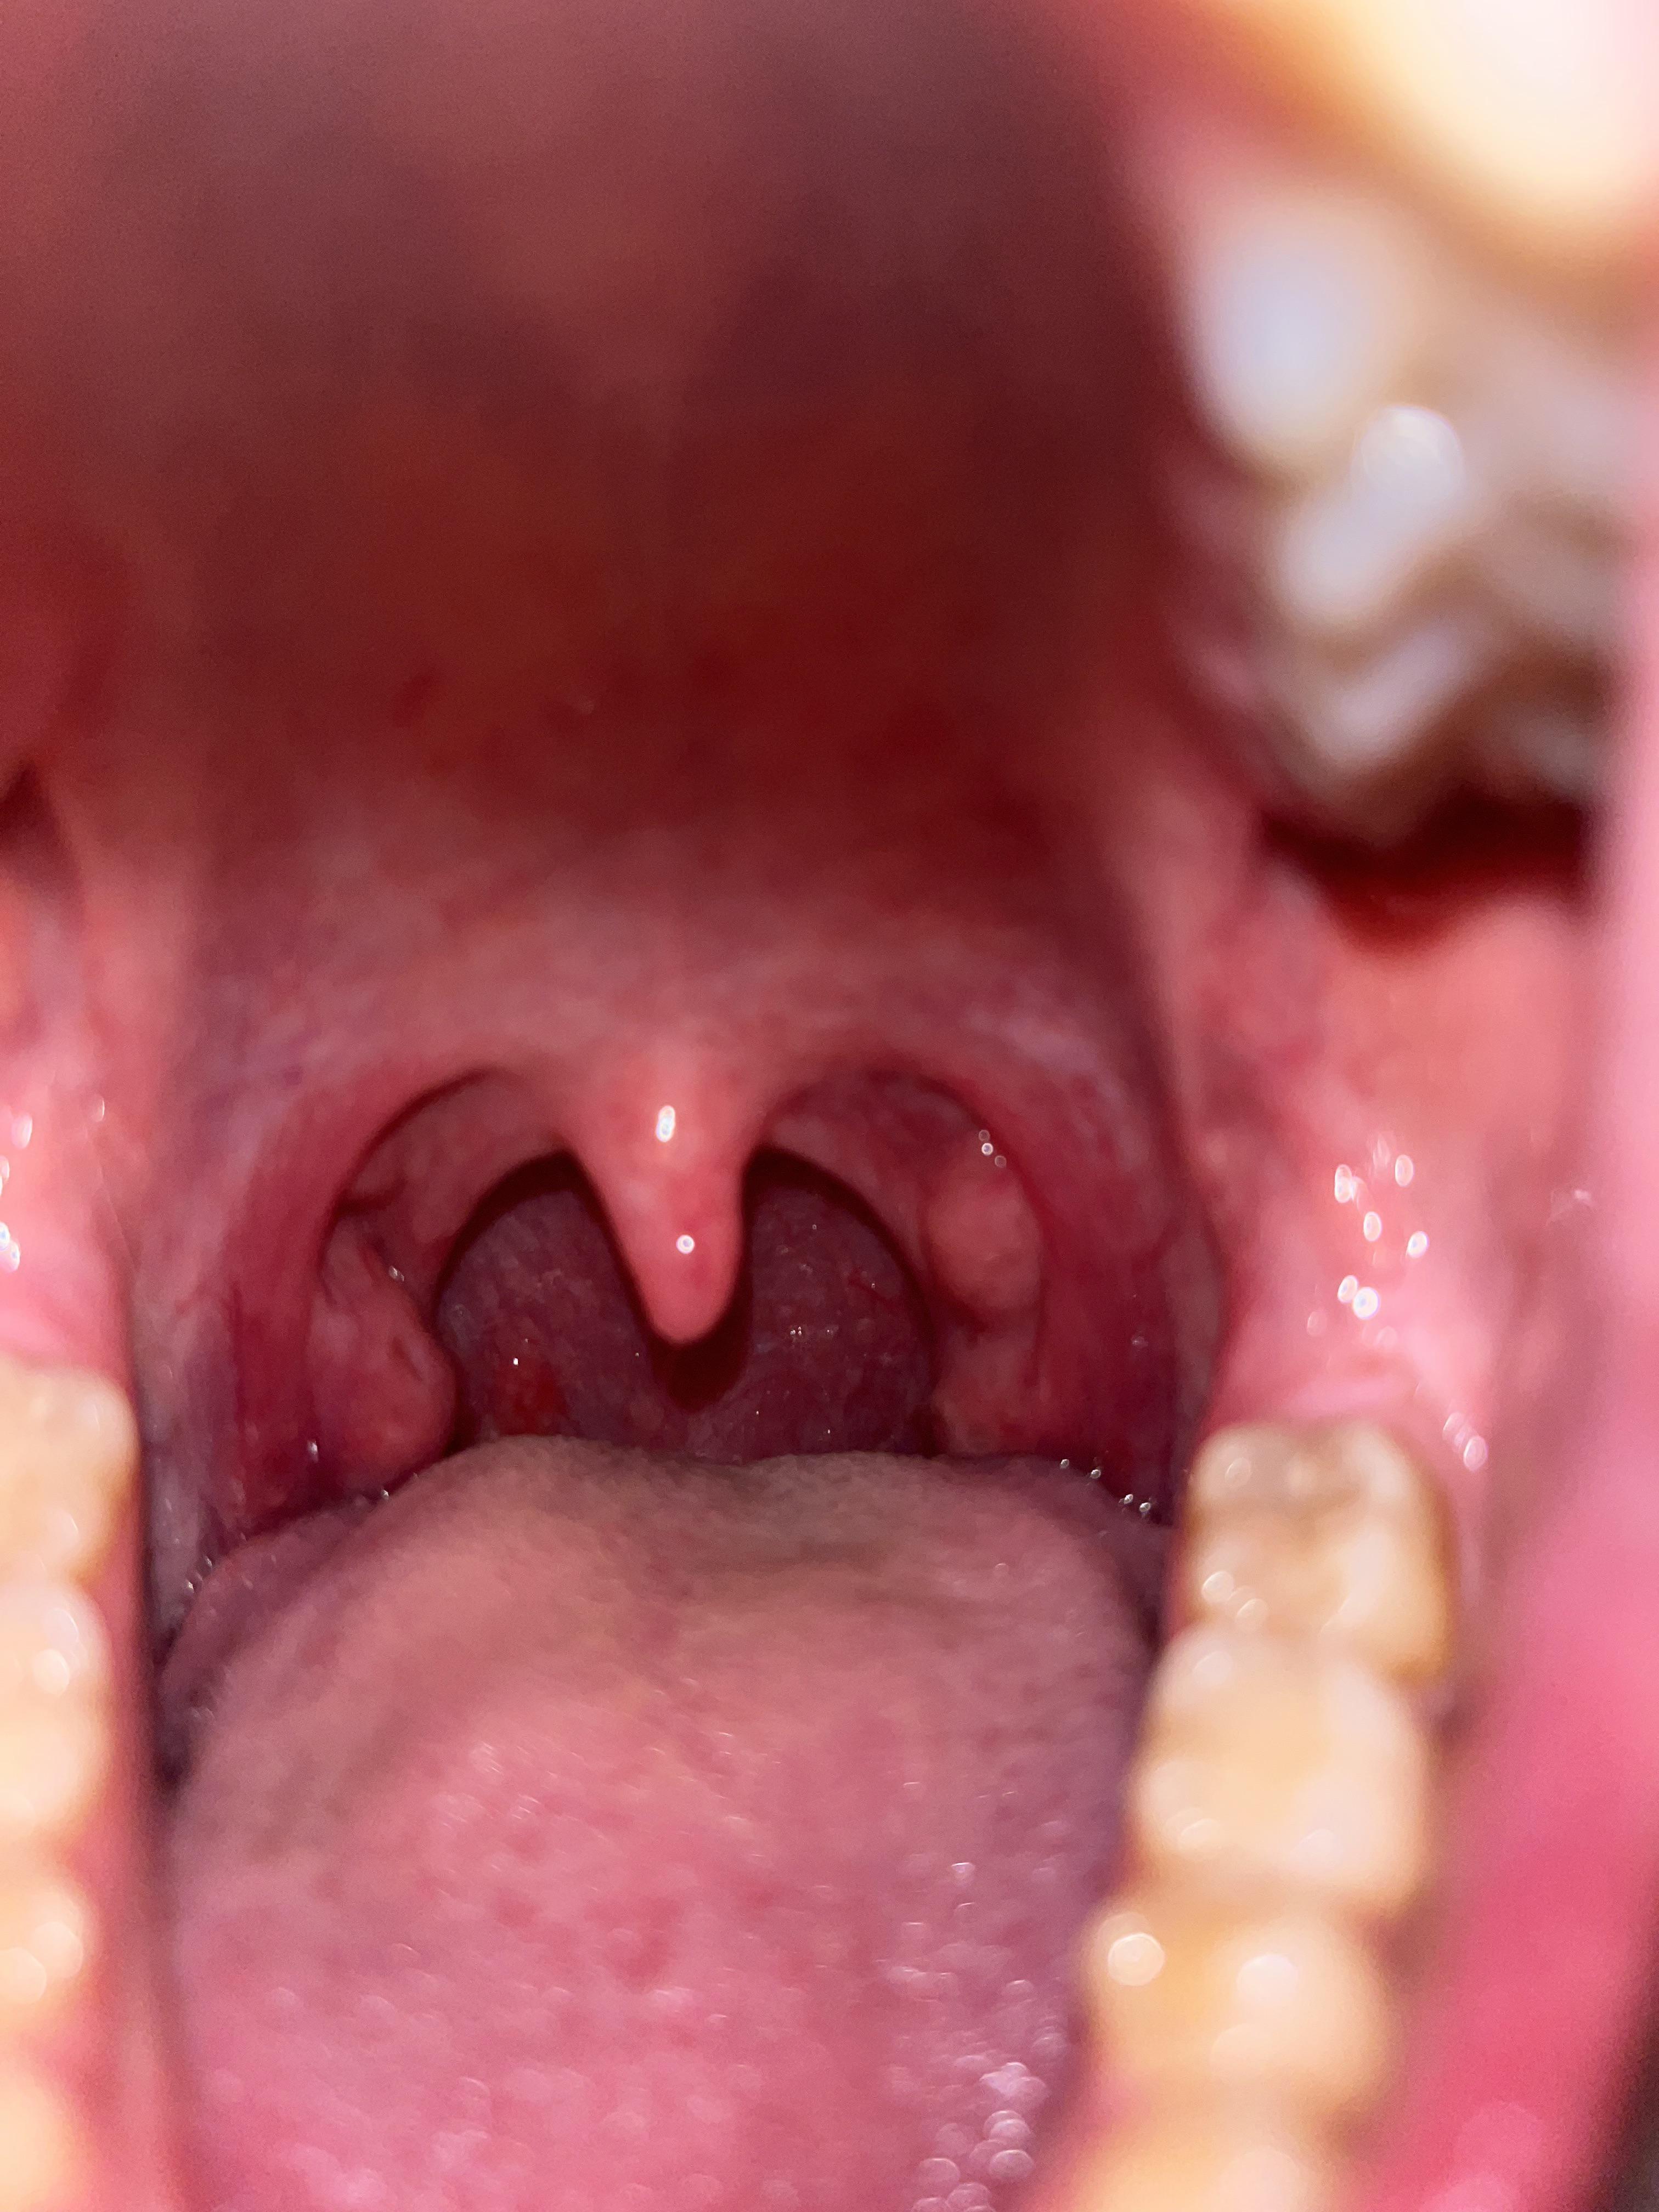

Tonsil Stones Getting Worse . Tonsil stones are caused by debris trapped in the tonsil crypts, and good oral hygiene can help reduce them. Learn the only way to fully prevent tonsil stones is to have your tonsils surgically removed. Tonsil stones are hard white or yellow formations that form in the crevices of your tonsils. Learn how to get rid of them with. They can cause bad breath, sore throat, and other problems. Find out why tonsil stones don't dissolve and when to see a. Find out how to practice good oral hygiene, remove tonsil stones at home, and when to see a. They are not harmful but can cause bad breath, irritation or infection. Tonsil stones are hardened substances that form in the crevices of your tonsils from food particles or mucus. Tonsil stones are small lumps of calcified material that form in your tonsils. There are several ways to remove tonsil stones, ranging from simple home remedies to professional treatments. They can cause bad breath, sore throat, earache and other symptoms. Learn how to remove them at home or. Learn about other preventive strategies, such as gargling, water flosser, and.

Tonsil Stones Getting Worse Tonsil stones are small lumps of calcified material that form in your tonsils. Tonsil stones are caused by debris trapped in the tonsil crypts, and good oral hygiene can help reduce them. Learn about other preventive strategies, such as gargling, water flosser, and. Learn how to get rid of them with. There are several ways to remove tonsil stones, ranging from simple home remedies to professional treatments. Find out how to practice good oral hygiene, remove tonsil stones at home, and when to see a. They can cause bad breath, sore throat, earache and other symptoms. They can cause bad breath, sore throat, and other problems. Learn how to remove them at home or. Find out why tonsil stones don't dissolve and when to see a. They are not harmful but can cause bad breath, irritation or infection. Tonsil stones are hardened substances that form in the crevices of your tonsils from food particles or mucus. Learn the only way to fully prevent tonsil stones is to have your tonsils surgically removed. Tonsil stones are hard white or yellow formations that form in the crevices of your tonsils. Tonsil stones are small lumps of calcified material that form in your tonsils.

Tonsil stones removal l Wrost Tonsil stones removal l Big Tonsil Stones Tonsil Stones Getting Worse Tonsil stones are caused by debris trapped in the tonsil crypts, and good oral hygiene can help reduce them. Tonsil stones are hardened substances that form in the crevices of your tonsils from food particles or mucus. Tonsil stones are small lumps of calcified material that form in your tonsils. They are not harmful but can cause bad breath, irritation. Tonsil Stones Getting Worse.